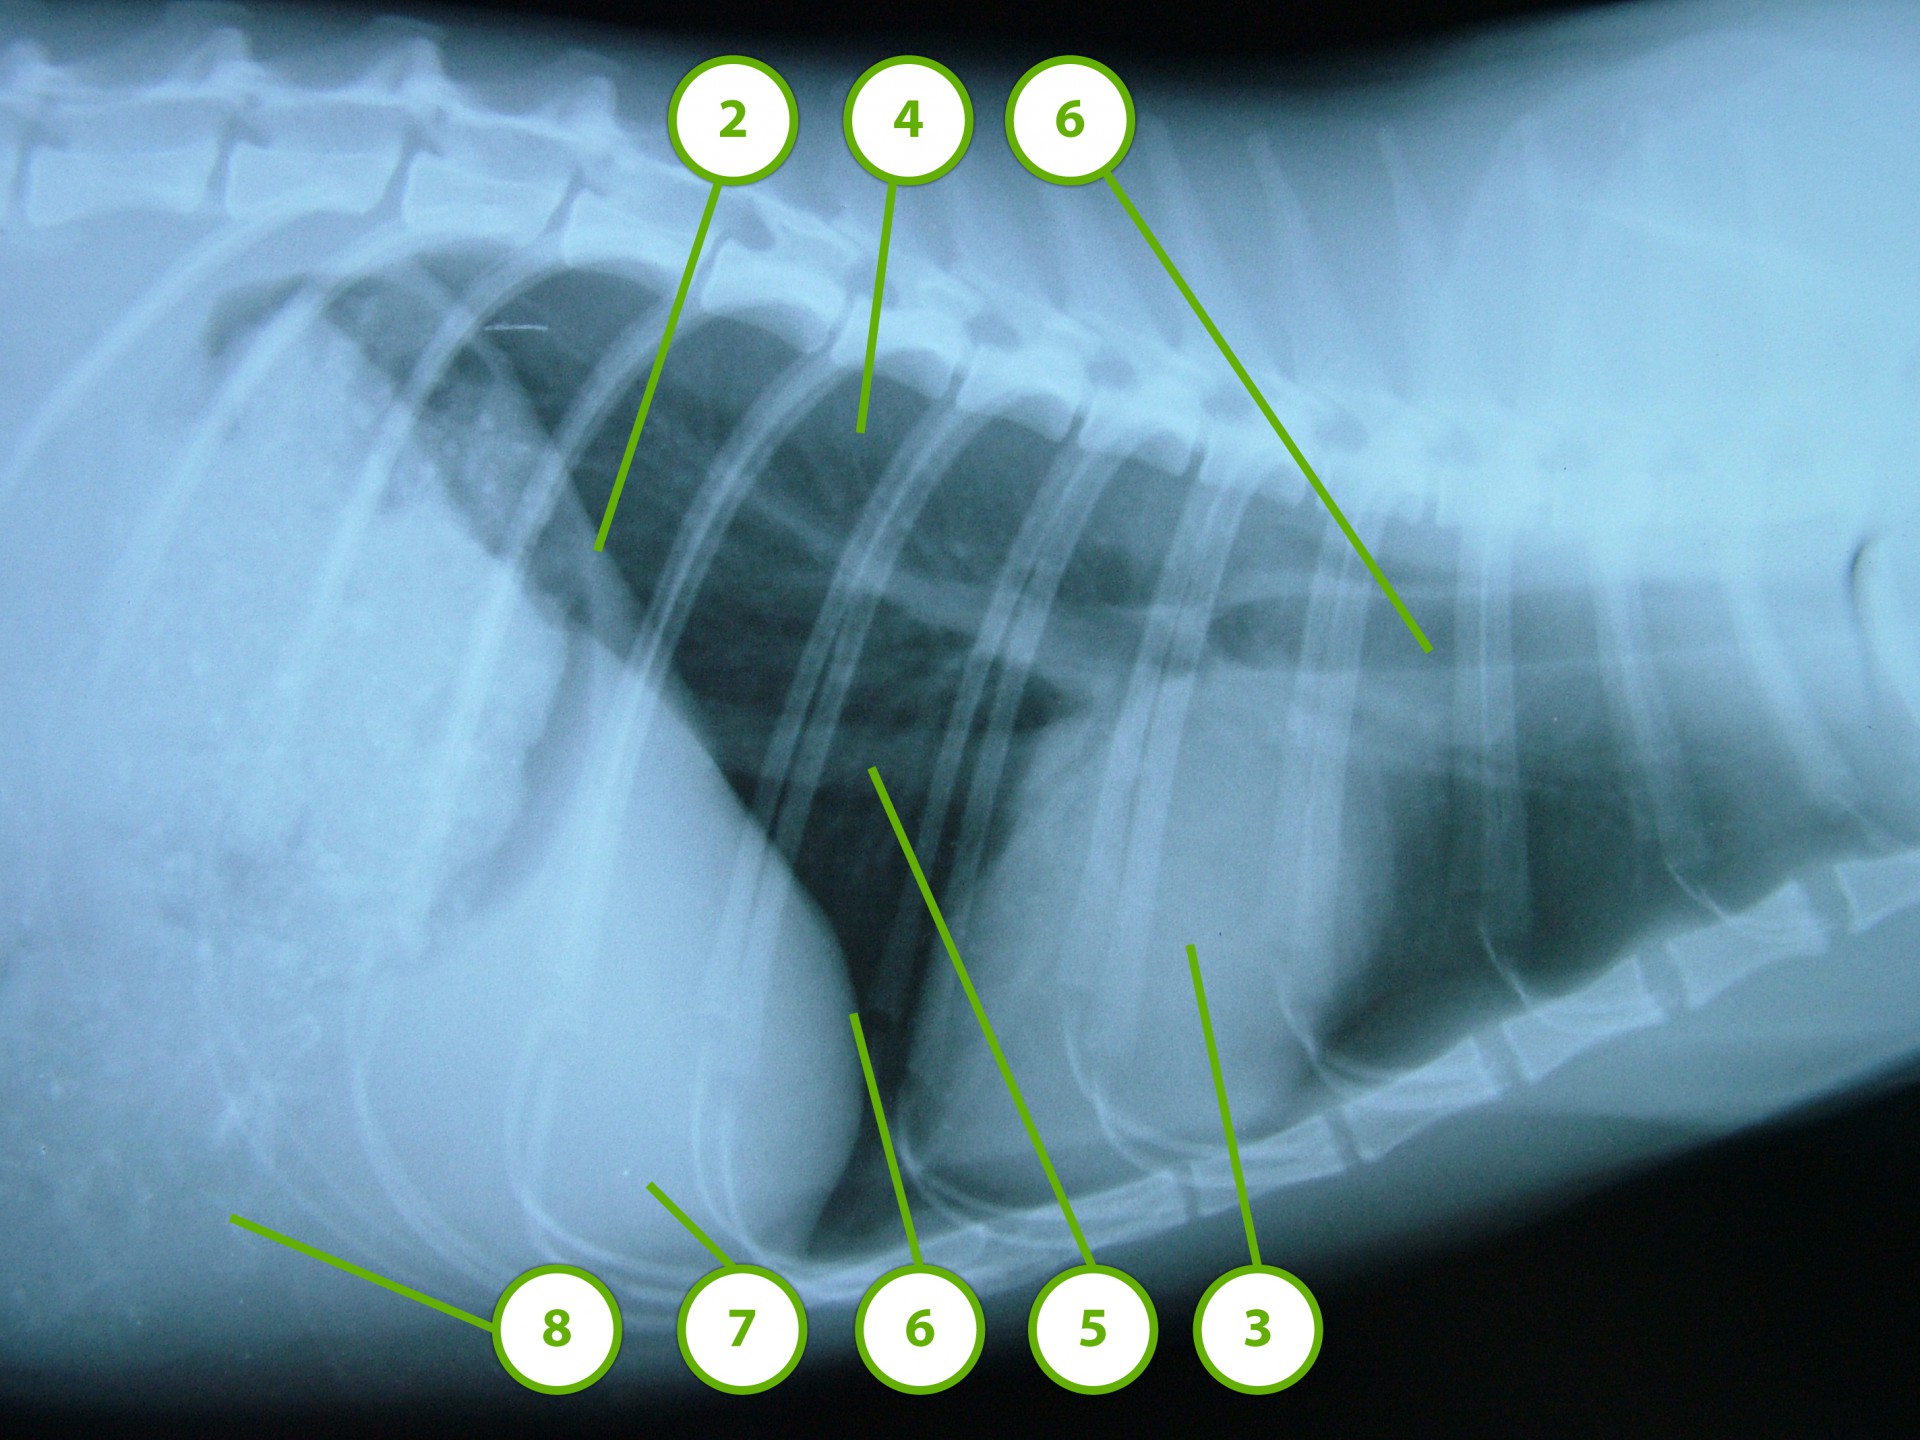

A rekeszizom veleszületett vagy szerzett sérülése, folytonosság hiánya következtében a hasüregi szervek a mellkasba nyomulnak, és összenyomják a tüdőt. Ennek következtében a tüdő nem képes a mellkas mozgását követni és elsősorban a belégzés folyamata korlátozottá válik.

• A fejlődési rendellenesség következtében kialakuló veleszületett rekeszsérv (hernia diaphragmatica congenitalis ) általában fiatal állatokban, alapvetően kétféle formában jelenik meg: az egyik formában a rekeszizom kisebb-nagyobb, a teljes vastagságára kiterjedő folytonossághiánya következtében a hasüregi szervek egy része a mellüregbe nyomul (valódi veleszületett rekeszsérv, hernia diaphragmatica congenitalis vara ).

Mindhárom rekeszsérv forma meglehetősen ritkán fordul elő. A diagnózis felállítása a kórelőzmény, a klinikai tünetek a mellkas röntgenvizsgálata, a hasüreg ultrahangos vizsgálata alapján lehetséges.A rekeszsérv műtéti ellátása során a legnagyobb kihívást az jelenti, hogy a hasüreg megnyitását követően a sérvkapun keresztül levegő kerül a mellüregbe, ezáltal az állat spontán légzése leáll, így a műtét teljes ideje alatt asszisztált lélegeztetésre van szüksége.A műtét során a mellkasba előesett szerveket reponáljuk, a rekesz folytonosság hiányát megszüntetjük és a mellkasban lévő szabad levegőt eltávolítjuk, ezzel biztosítva az állat spontán légzését. A műtétet követő napokban legfontosabb feladat a vérkeringés és a légzés folyamatos, kórházi körülmények közötti kontrolálása.Az idejében felismert és megfelelően ellátott veleszületett rekeszsérv jó eséllyel gyógyítható, a traumás eredetű sérv ellátásának eredményességét általában az egyéb szervek sérülése határozza meg.